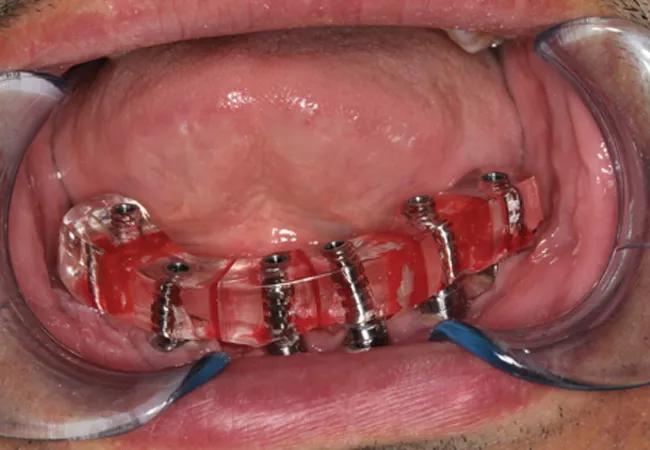

On presentation for prosthetic reconstruction, the thickness of the fibula free flap revealed that standard metal impression copings were unusable as they were buried under the free flap. Special abutments were connected to implants in order to traverse the free flap tissue transmucosally for prosthetic connection and correction of any minor angulation issues with the implants. Impressions of the implants were made to capture all implant positions.

The patient subsequently underwent surgical placement of six bone-level implants into the reconstructed mandible

Figure 6

A verification index (Figure 6) was then transferred intraorally to check accuracy of the implants captured. Next, a mandibular fixed complete denture prosthesis was designed and fabricated based on where the patient’s bite would have been prior to surgery. The inserted prosthesis helped restore the patient and make up for the lost bone, tissue and tooth height (figure 7). This patient left for Kuwait to be with his family in very high spirits, and a two-year treatment plan finally came to fruition. His family can see him smiling once again.

A verification index